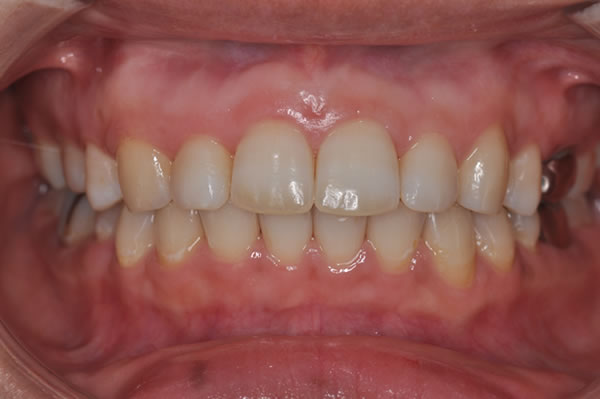

上顎前突症の治療例

上顎前突症(出っ歯)の矯正症例 ケース01

上顎前突症(出っ歯)の矯正症例 ケース02